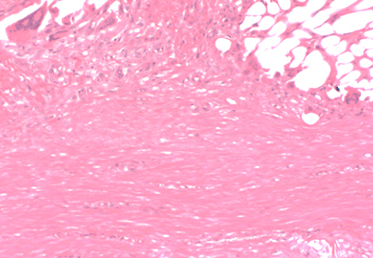

Bild der porösen Struktur von Biobrace

Bild einer mit neuem Gewebe gefüllten Bio-Orthese

Die poröse Struktur des BioBrace®-Implantats

Schnelle Zellinfiltration: Das hochporöse Gerüst bietet die ideale Umgebung für die Zellinfiltration und -proliferation, um neues, funktionelles Gewebe zu bilden.

Das BioBrace®-Implantat, gefüllt mit neuem Gewebe

Ausgerichtete Neubildung von Gewebe: Die fortschrittliche 3D-Struktur von BioBrace® bietet interne Kanäle, die die Ausrichtung neuer Fasern auf natürliche Weise steuern.